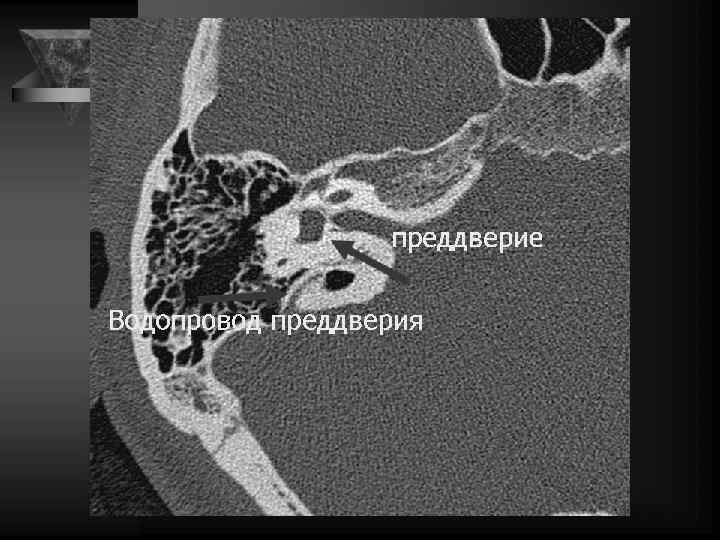

Внутреннее ухо и верхушка пирамиды • Улитка: деминерал-я костной капсулы, спирал-й канал улитки и его просвет, оссификация • Преддверие и полукружные каналы, интактные стенки, оссификация • Внутр. слух. проход: расширение, неровн-ть контура, деструкция кости, стеноз • Канал лицев. нерва до коленч. ганглия. • Водопровод преддв-я и водопр. улитки. • Верхушка пирамиды: губчатая или пневматизирована, наличие секрета, наличие образований

Перепончатый лабиринт (ПЛ) включает органы равновесия - мешочки преддверия и полукр. протоки, а также орган слуха, расп-й в улитковом протоке. В передней части перепончатого лабиринта - улитковый проток, соединительный проток улитки и сферический мешочек. Задняя часть ПЛ состоит из эллиптического мешочка, полукружных протоков и эндолимфатического протока с его мешком (аппарат равновесия).